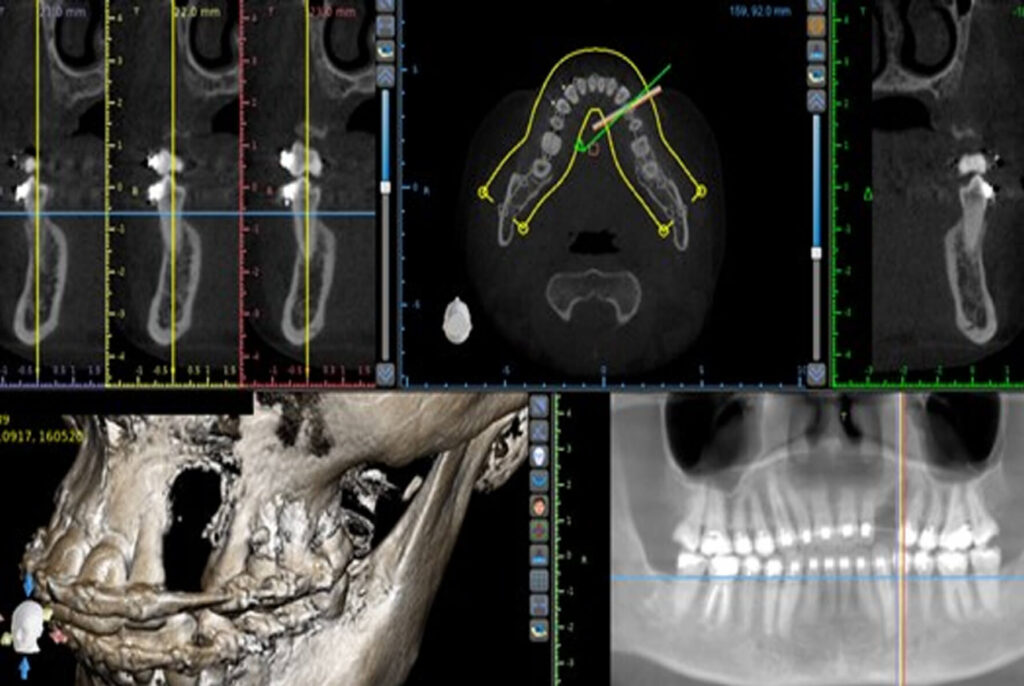

A 30-year-old female patient was referred for an implant restoration in the left upper canine area. In order to acquire a

precise assessment of the tridimensional bone volume, a Cone Beam CT scan was taken which revealed a vertical osseous deficiency (fig 1). Prior to the implant installation a surgical vertical augmentation became necessary so that the

implant could be placed in a tridimensional correct position (fig 2).

Figure 1 – CT scan showing vertical

deficiency.